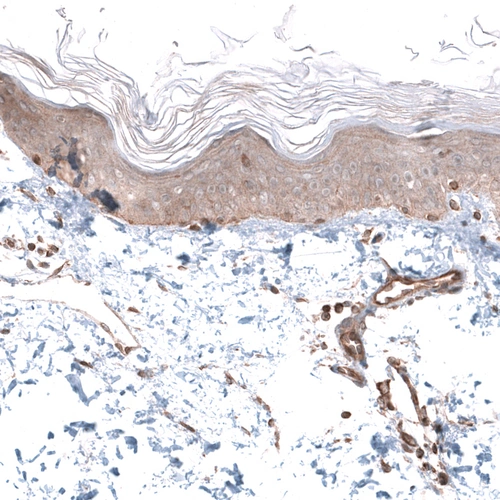

Immunohistochemical staining of human skeletal muscle shows strong cytoplasmic positivity in myocytes.